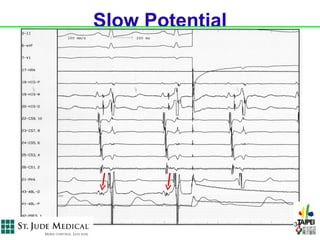

•   Electrogram approach: 小 A, 大 V (slow

potential)

Slow Potential

34